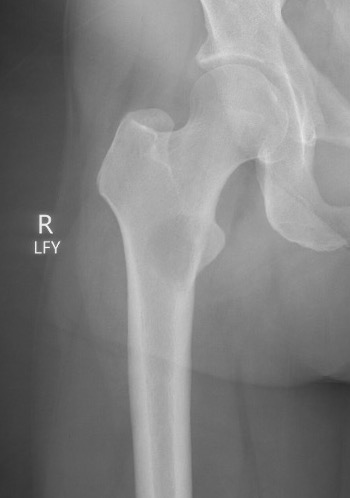

Femoral neck stabilization

Issues

- sufficient bone for fixation?

- determine if lesions further down femur (xray entire femur)

- consider augmentation with PMMA / cement